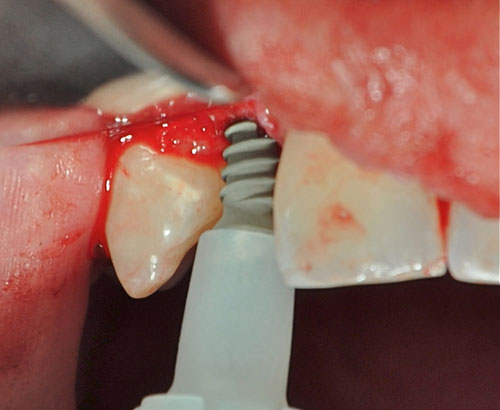

Abordamos con fresa lanceolada para el marcaje del lecho y expandimos con expansores roscados para densificar un hueso de Tipo IV

Instalamos los implantes manualmente y aplicamos dos abuttments temporarios a fin de restaurar en forma inmediata y suturamos.

Instalación de implantes

Instalación de implantes

Instalación de implantes

Instalación de implantes

Abbutments temporarios

Tallado de los Abbutments